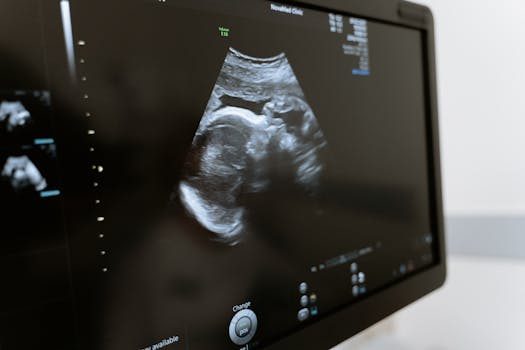

Después de tener la regla puedo estar embarazada: ¿es posible?

La posibilidad de quedar embarazada es un tema que genera muchas dudas entre las mujeres. Después de tener la regla, es natural preguntarse si se puede concebir. En este artículo, abordaremos diversas preguntas relacionadas con el embarazo y la menstruación para brindarte información clara y precisa.

Es importante entender el funcionamiento del ciclo menstrual y los momentos en los que hay mayor riesgo de embarazo. A lo largo del contenido, responderemos a preguntas frecuentes y proporcionaremos información vital sobre la salud reproductiva.